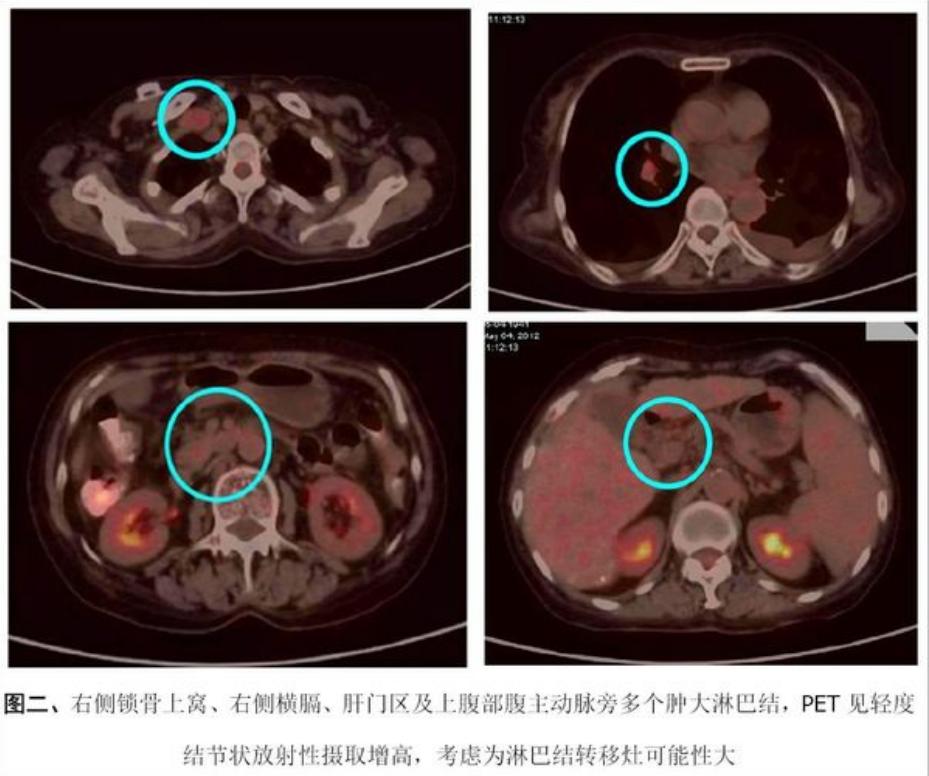

2012-5-4行PET/CT检查,结果如下:

从查出肝癌到癌症复发转移,只用了不到三个月的时间,陈女士都不敢相信病情会进展得这么快,但是她和她的家人都不想放弃,辗转打听联系到田主任。